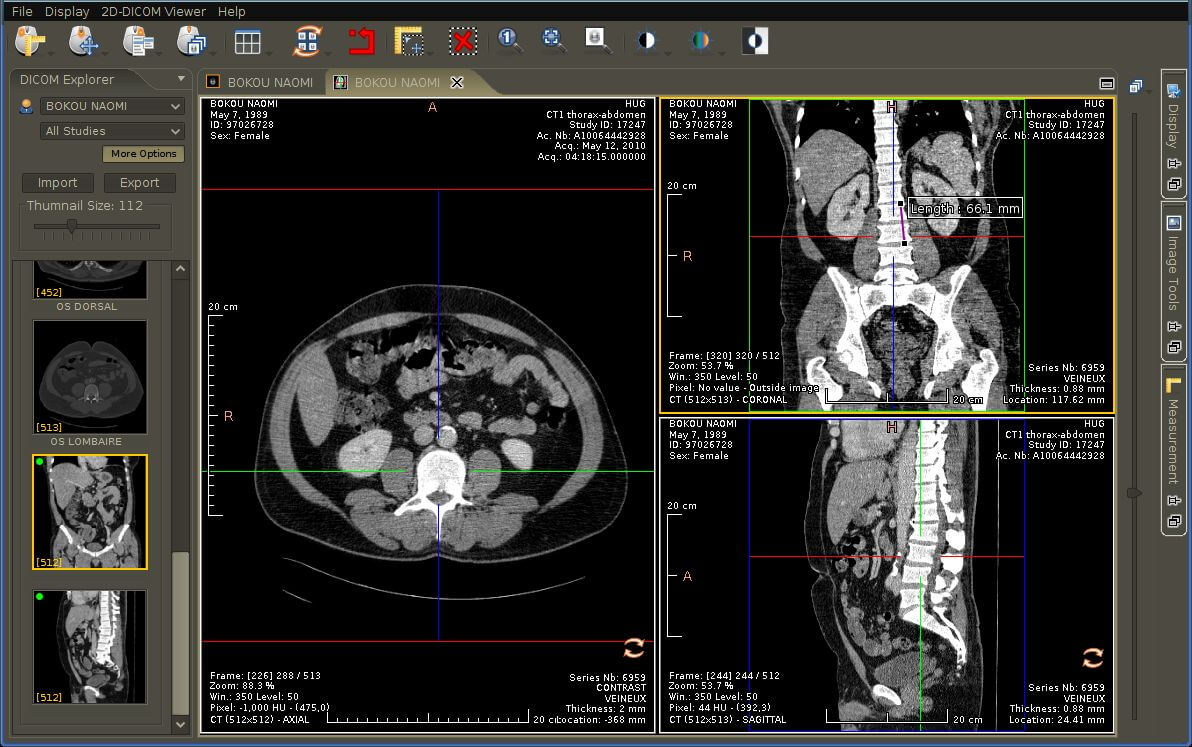

The RadiAnt DICOM image viewer is a simple, fast platform that is compatible with Windows. It offers multiple features, including MPR, MIP, and image fusion. Images can be exported to JPEG, PNG, and other image formats. They can also be copy-pasted directly to presentations and word documents.

The application is just a viewer and does not offer storage space. Their website has a disclaimer explicitly stating that they do not have any certifications, and as such, the product is not intended for diagnostic use. However, it is handy for students and residents for studying medical images and research purposes.